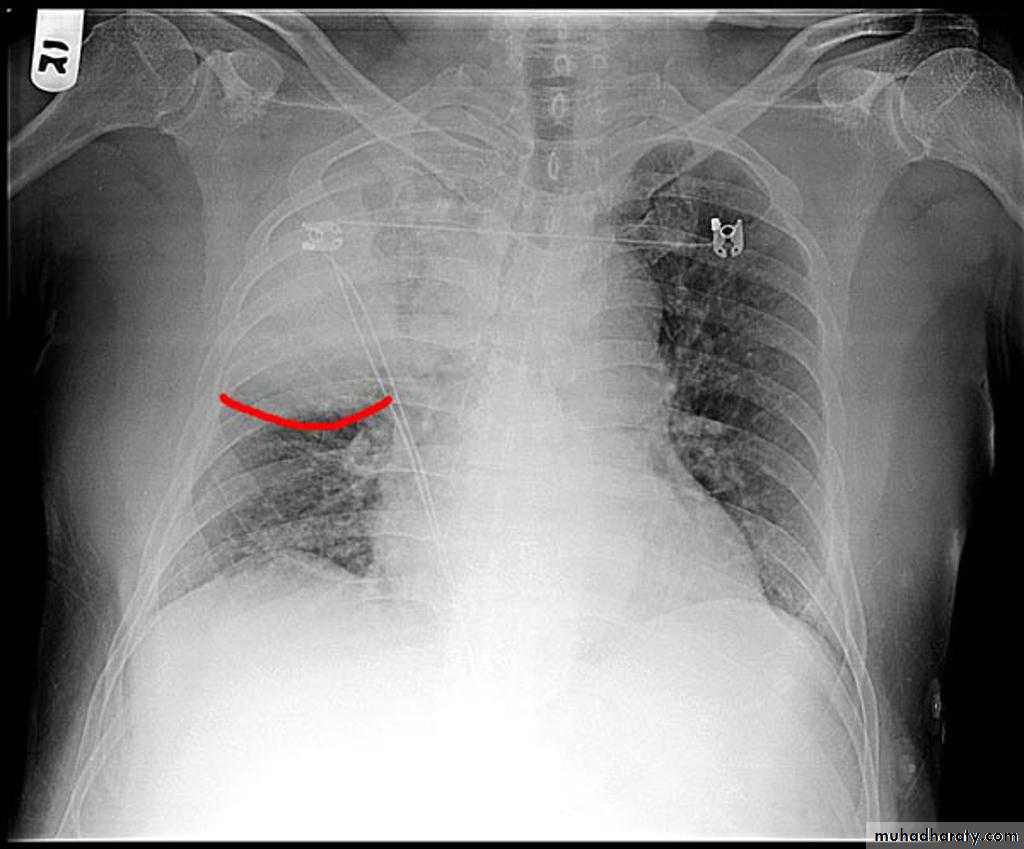

Hydro pneumothorax

58.hydropneumothorax